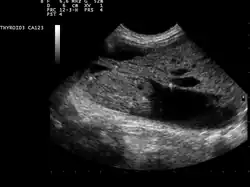

Обычно пальпаторно выявляются узлы, размеры которых превышают 1 см. С помощью датчика (частота 7,5 МГц) проводится эхоскопия (ультразвуковое исследование щитовидной железы). Метод существенно расширяет возможности практикующих врачей на этапе диагностического поиска — позволяет не только выявить дополнительное образование в щитовидной железе, но и установить основные признаки узла: характер роста, наличие капсулы, кальцинатов, фиброза, жидкости или коллоида внутри узла.

Заболевание чаще развивается у женщин в возрасте 50—60 лет, длительно проживающих в условиях природного дефицита йода и страдающих многоузловым эутиреоидным зобом. Причины возникновения заболевания полностью не изучены. Клиническая симптоматика при многоузловом токсическом зобе аналогична симптоматике вышеизложенных заболеваний, протекающих с синдромом тиреотоксикоза. Отсутствуют офтальмопатия и претибиальная микседема. При физикальном исследовании определяется несколько узлов, как правило, округлой формы, образующих единый конгломерат или не связанных между собой, с гладкой поверхностью, четкими контурами, смещаемых при глотании с щитовидной железой. Ультразвуковая картина соответствует данным физикального исследования. Иногда при помощи УЗИ выявляются дополнительные непальпируе- мые узлы. Контуры узлов четкие, структура однородная, эхогенность, как правило, выше по сравнению с экстранодулярной тканью щитовидной железы. На основании радионуклидного сканирования выделяют три формы многоузлового поражения щитовидной железы, протекающих с синдромом тиреотоксикоза: многоузловой зоб с гиперфункционирующими узлами и нефункционирующей экстранодулярной паренхимой (60—80 %); многоузловой зоб с нефункционирующими узлами и гиперфункционирующей экстранодулярной паренхимой (10—20 %); многоузловой зоб, при котором одновременно гиперфункционируют и узлы, и экстранодулярная паренхима (3-5 %). Для исключения рака щитовидной железы необходимо производить тонкоигольную аспирационную биопсию и цитологическое исследование. С этой целью пунктируют каждый узел и экстранодулярную паренхиму обеих долей щитовидной железы.